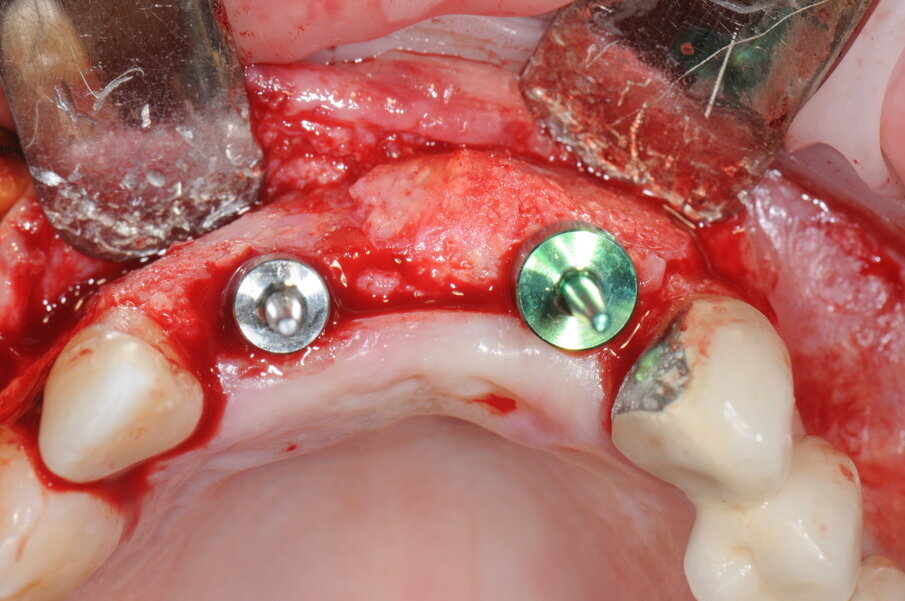

Seconda fase di chirurgica

A 9 mesi è stata effettuata la seconda fase chirurgica in cui era prevista la rimozione delle viti di osteosintesi e il posizionamento degli impianti nei siti 1.1 e 1.2 (Blossomâ Intra-Lock System Europa). Grazie al volume osseo rigenerato risultava adeguato il posizionamento degli impianti come da progettazione protesica iniziale (Figg. 16-19).

Fig. 16 - Esposizione del sito rigenerato in visione occlusale.

Fig. 17 - Preparazione del sito implantare; impianti Blossom Intra-Lock.

Fig. 18 - Posizionamento delle viti tappo.

Fig. 19 - Sutura del lembo.